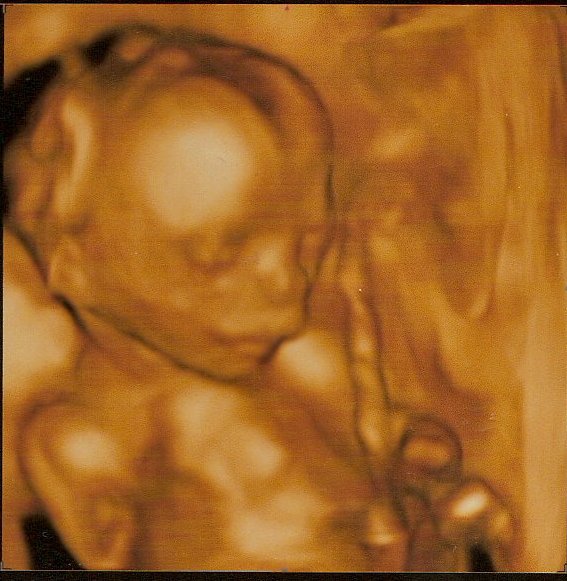

tak mám radost samozřejmě.... jinak bych řekla Lucy že to první video v tom 13 TT je asi peknejsi..tady vicemene točila jen hlavičku a ta vypadá z mnoha uhlu podivně :-) ale mám jednu peknou fotku kde se podle mě usmívá